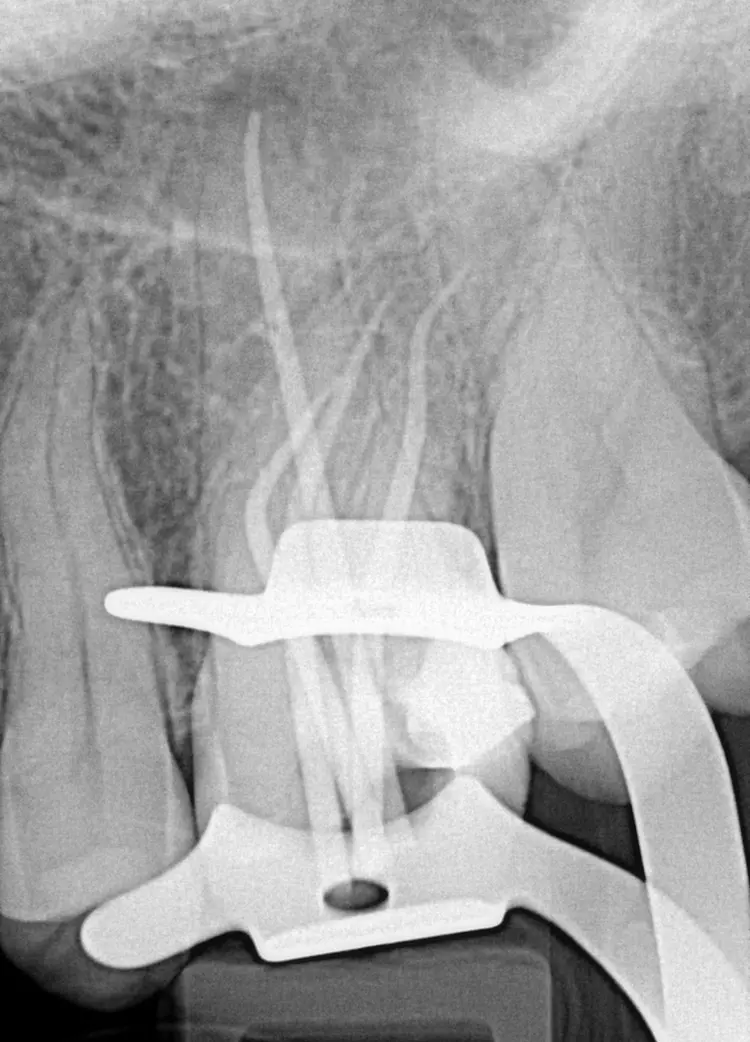

Da die zweidimensionale Diagnostik aufgrund der Länge der Wurzeln erschwert war und sich zudem eine komplexe Anatomie vermuten ließ (Abb. 1), wurde zur erweiterten Diagnostik und zur Behandlungsplanung ein kleinvolumiges DVT angefertigt (Orthophos SL, Dentsply Sirona, Volumen Ø 5 x 5 cm, Auflösung 80 μm). In der DVT-Aufnahme zeigte sich eine apikale Osteolyse an der palatinalen Wurzelspitze mit reaktiver Schwellung der angrenzenden basalen Kieferhöhlenschleimhaut (Abb. 2). Der periapikale Knochen an den vestibulären Wurzeln stellte sich unauffällig dar.

Eine apikale Fusion der Wurzeln mit zusätzlicher Konfluation des mesio-bukkalen und des disto-bukkalen Kanals wie bei Zahn 27 lag an dem zu behandelnden Zahn nicht vor. Die Wurzelkanalmorphologie (Krümmung, Konfluation) der mesiobukkalen Wurzelkanäle von Zahn 26 ließ sich gut anhand verschiedener axialer Ebenen (Abb. 3) erkennen und mit Hilfe einer Planungssoftware (SICAT Endo, SICAT) dreidimensional visualisieren (Abb. 4). Da in diesem Fall der zweite mesio-bukkale Kanal eine Krümmung sowohl in distaler Richtung als auch nach vestibulär aufwies, wurde vorab geplant, den Kanal lediglich bis zur Konfluation mechanisch zu erweitern.